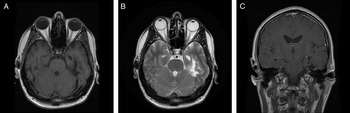

Magnetic resonance imaging of the brain revealed multiple abnormalities (Figure 1) including left mesial temporal encephalomalacia and T2-weighted imaging hyperintensities scattered throughout the supratentorial white matter. There was no abnormal enhancement.

Figure 1: Neuroimaging findings. Axial T1-weighted image (A), axial T2-weighted image (B), and coronal T1-weighted image with gadolinium (C) demonstrate left mesial temporal encephalomalacia and atrophy.

Classically, there is no identifiable underlying pathology of HC; however, increasing numbers of symptomatic cases have been reported. Head trauma is a rare cause of HC, and this represents the first case due to a temporal lobe lesion. Such cases have been referred to as ‘secondary HC’ in the literature Reference Prakash, Shah and Soni3,Reference Prakash and Patel4 ; however, a more accurate diagnosis in accordance with The International Classification of Headache Disorders, 3rd edition (ICHD-3) is persistent headache attributed to moderate or severe traumatic injury to the head with clinical features consistent with HC. 5 While the relationship between TBI and onset of headache with features of HC may be spurious, the temporal relation in this case suggests causation. The authors hypothesize that the connections between the mesial temporal lobe and the posterior hypothalamus were disrupted, resulting in clinical HC.